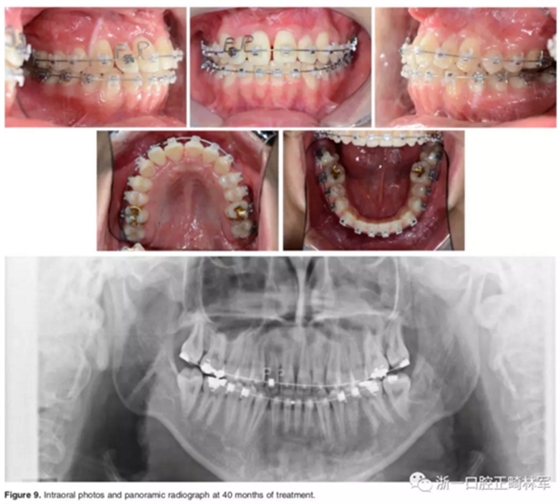

結(jié)束階段:

治療40個(gè)月后,3顆阻生牙位置已靠攏,繼續(xù)進(jìn)行排齊。使用高轉(zhuǎn)矩托槽及帶L型曲的0.019*0.025-inch Beta鈦絲對側(cè)切牙進(jìn)行轉(zhuǎn)矩控制,再在雙頜使用0.019*0.025-inch不銹鋼絲進(jìn)行排齊。矯治結(jié)束后,去除托槽、弓絲,雙頜前牙區(qū)粘接保持器。

總療程約50個(gè)月。

口外相:前牙易位、阻生均得以正確糾正,牙周組織健康。

口內(nèi)相及模型:I類尖牙、磨牙關(guān)系,覆合、覆蓋正常;中切牙與側(cè)切牙間有輕微的轉(zhuǎn)矩差;牙齦外形可;此外,在治療期間病人的口腔衛(wèi)生不夠良好,導(dǎo)致幾顆牙齒出現(xiàn)了齲病。

影像學(xué):頭顱側(cè)位片示:矢狀向和垂直向骨骼發(fā)生變化(ANB角,3°;SN-MP,51°);上頜切牙略前傾(U1-SN,106°),與下頜切牙一致(IMPA,75°);病人的面部輪廓得以保持。全景片示:由于牙齒萌出,上前牙區(qū)垂直向牙槽骨水平增加;雖然前牙牙根較彎曲,但其平行度仍可,且無明顯的牙根吸收。CBCT示:前牙唇側(cè)骨質(zhì)連續(xù)性改善,牙根唇側(cè)支持組織變好,牙槽骨高度、厚度均有增加,但轉(zhuǎn)矩的改變一定程度上導(dǎo)致了局部應(yīng)力的增大。